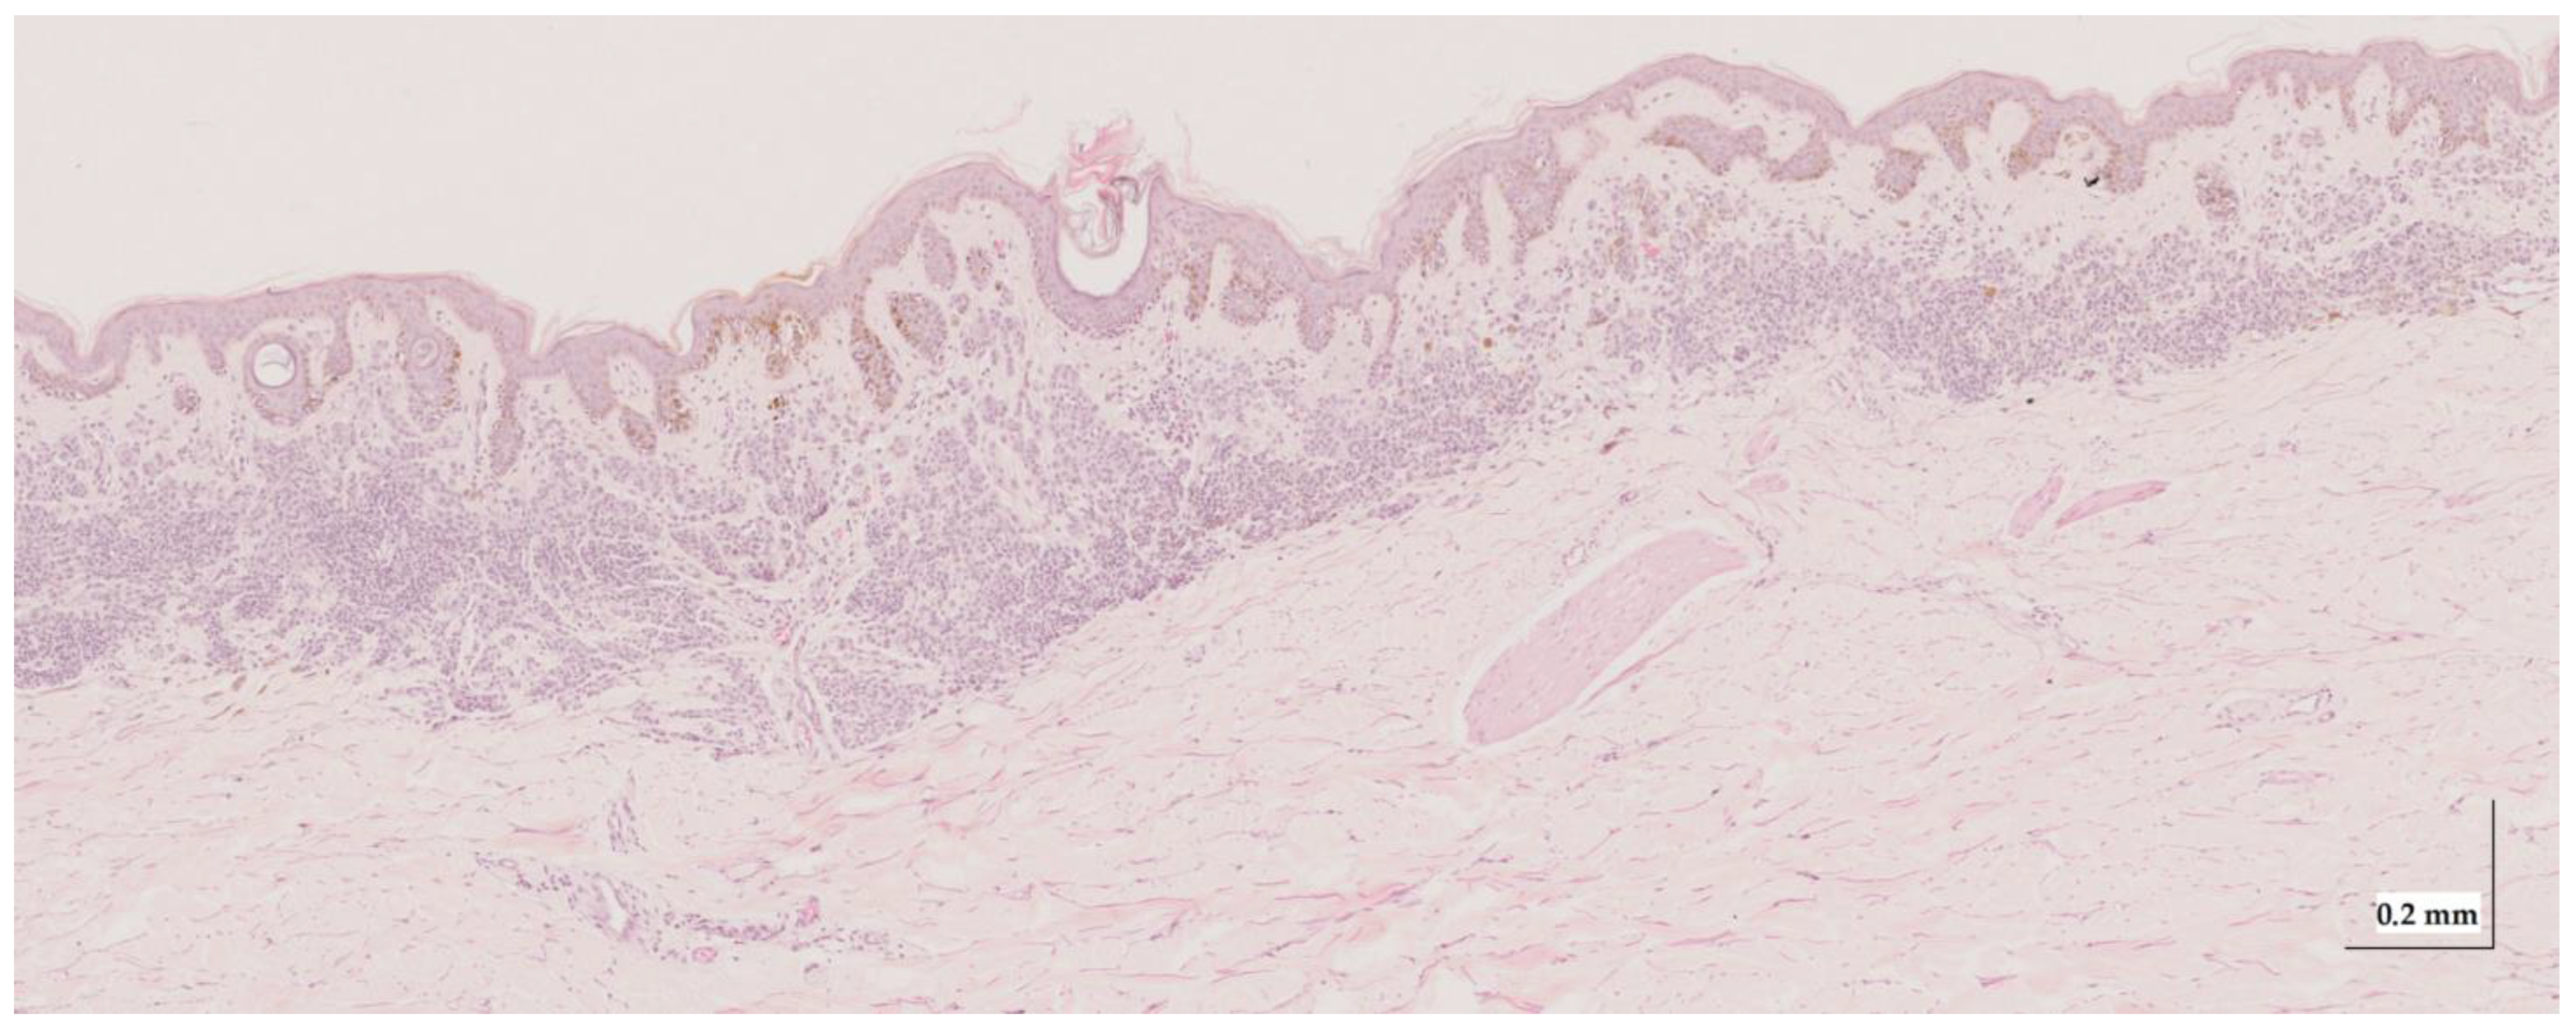

Appendix A. Selected Cases Studies’ HE Histopathological Images (Limited to OCT FOV)

| Intradermal nevus (IN) Case 1 | Localization: right forefoot (sole) |

![]() | ![]() |